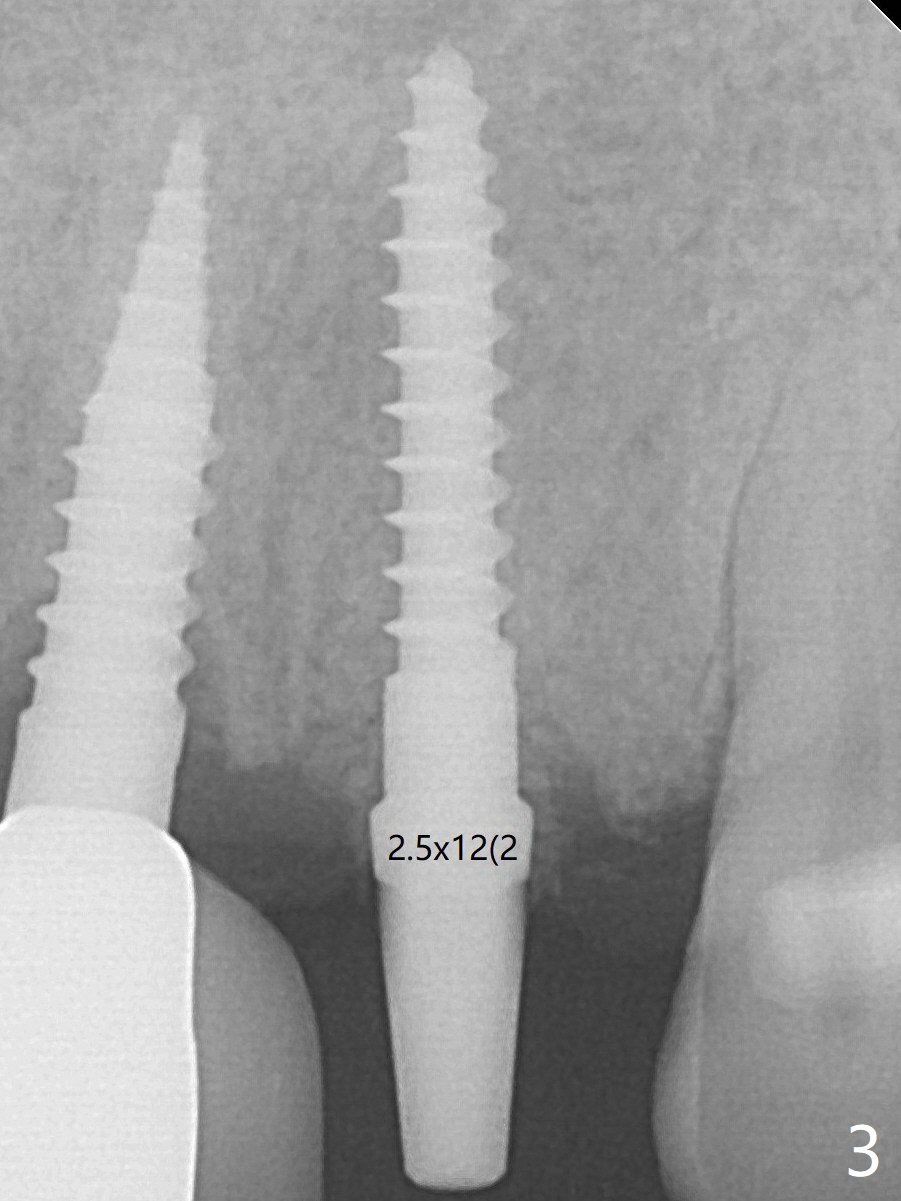

Following trajectory confirmation (Fig.2), a 2.5x12(2) mm implant is placed a little deeper than expected to ensure no implant thread exposure with bone graft (Fig.3).  The threads appears to be covered by the bone or bone graft 4 months postop (Fig.6).